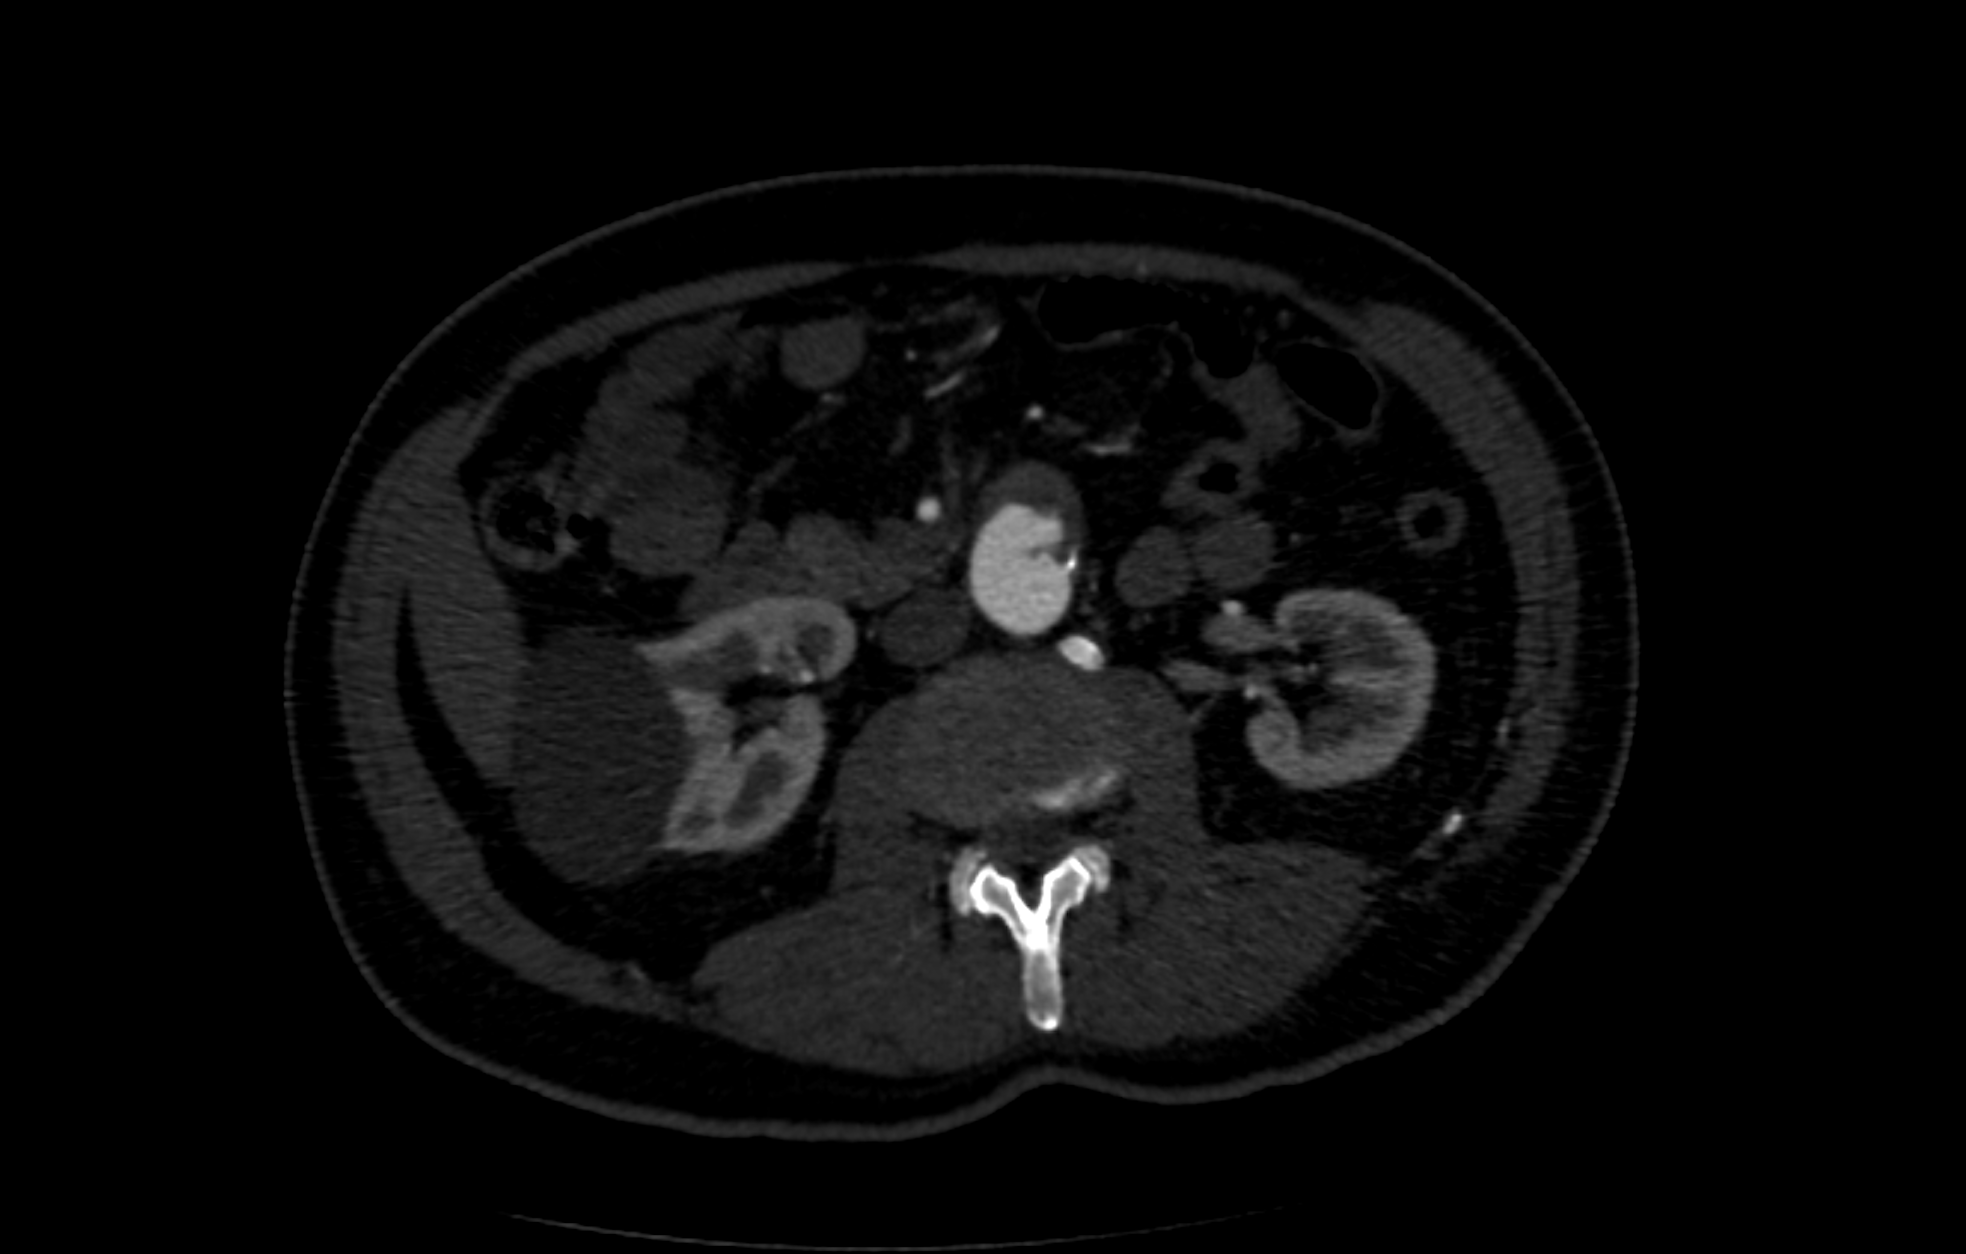

Refer to caption

(b) Coronal slice of a CTA scan. Different shades of grey differentiate between different organs and tissues. This allows both the clinicians to see the entire anatomy of the patient and the algorithm to execute the segmentation process.

Figure 1: Schematic representation of an Abdominal Aortic Aneurysm and a CTA scan.

3.1 CTA scans

The most used and effective method for anatomy visualization is Computed Tomography Angiography. CTA is used to get a visualization of the human body and is realized with emission of X-rays through a tomograph. A CTA scan consists of a 3-dimensional image of a region of interest in the form of a volume composed by voxels with different shades of grey. Each shade is associated to a different tissue, making it possible to distinguish not only between fat, bones and muscle but also artery, intraluminal thrombus (ILT) and calcification - see also Figure 1(b).